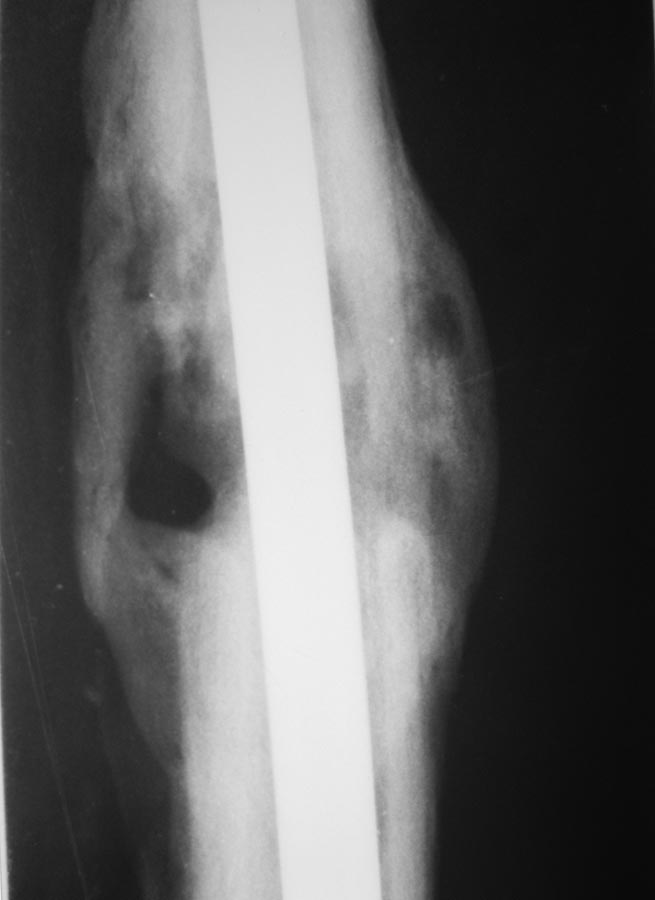

Уважаемые коллеги, представляют на обсуждение клинический случай! Пациент 26 лет, около года назад получил травму в результате ДТП. По поводу перелома диафиза бедренной кости выполнялся БИОС.

Заживление ран в области дистальных блокирующих винтов происходило вторичным натяжением, однако, в ходе местного лечения раны зажили.

Спустя 4-5 мес. пациент обратился с болями в нижней трети бедра (проекция дистальных блок. винтов). При RG выявлена их миграция, выполнено их удаление.

Спустя еще 4-5 мес обратился с жалобами на припухлость в области дистального блокирования. В поликлинике сделали снимки и, с подозрением на остеомиелит, оправили в стационар.

Сегодня: местно - без признаков инфекции. В области дистального блокирования припухлость плотно-эластичной консистенции. При пункции получить ничего не удалось. Лейкоциты 6,0; СОЭ - 22. СРБ-18. Температура в вечерние часы 37-37,2

Снимки представлены.

Какова дальнейшая тактика?